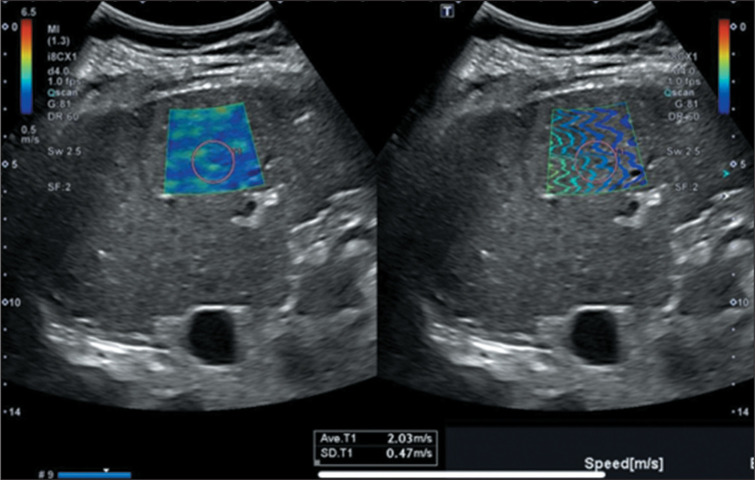

This study aimed to systematically review the highest-quality evidence regarding the cutoff value in kPa for the diagnostic accuracy of ultrasound-based liver elastography in comparison with reference standards, including magnetic resonance imaging (MRI), computed tomography, and liver biopsy. In addition, we assessed the presence of hepatocellular carcinoma (HCC) and its associated implications in clinical and diagnostic contexts. We conducted a search using Medical Subject Headings across PubMed, Embase, Cochrane Library, Web of Science, Scopus, and Lilacs for articles published up to June 6, 2024. Of 1,131 studies identified, 33 were eligible and 8 met the quality criteria, as evaluated with the "RTI Item Bank" and "QUADAS-2" tools, following the PICO strategy. The mean elasticity of the liver parenchyma among patients with confirmed HCC was 18.77 kPa (95% CI: 16.28-21.27), making ultrasound liver elastography useful as a predictor of the diagnosis by gold-standard methods such as MRI. Ultrasound elastography is a low-cost, accessible, and noninvasive diagnostic tool capable of estimating liver elasticity in patients with HCC. However, due to the heterogeneity of the articles included in this review, further prospective studies are needed in order to confirm and standardize a cutoff stiffness value for early HCC screening, which could improve patient outcomes, particularly in resource-limited settings.

Abstract Image